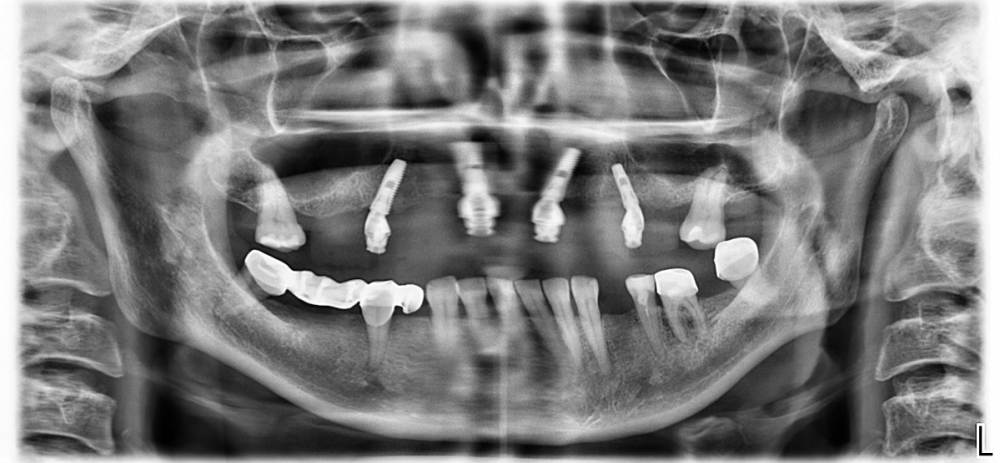

Malova Опубликовано 6 августа, 2021 Поделиться Опубликовано 6 августа, 2021 Добрый день! Установили импланты в прошлом году, система все на 4. После установки снимки врач не делал, сделала ортопантограмму сама. Очень необходим профессиональный взгляд в установке имплантов, пока не подписан акт приема передачи работы. Спасибо большое всем, кто отзовётся! Ссылка на комментарий

Irouil Опубликовано 6 августа, 2021 Поделиться Опубликовано 6 августа, 2021 Ортопантомограмма выглядит нормально 1 1 Ссылка на комментарий